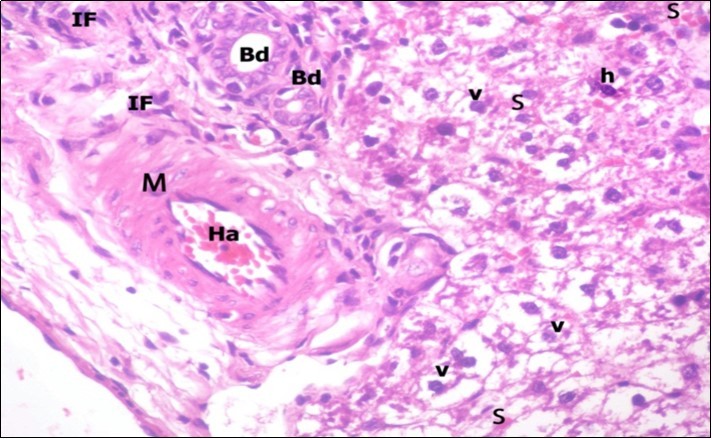

Examination of H&E stained sections of the 1st group (control group) revealed hepatic architecture of tightly packed cords of hepatocyte with vesicular nuclei and acidophilic cytoplasm radiating from the central vein (Figure 1). Portal area was composed of a portal vein, branch of hepatic artery and bile duct lined by single cuboidal cells with dark rounded nuclei. Blood sinusoids with their endothelial lining of Kuppfer cells were noticed in between hepatic cords (Figure 2). Examination of the liver sections of the 2nd group (vitamin E treated group) showed nearly the same histological features as the 1st group. The 3rd group (ZnONPs-treated group) showed a marked loss of the normal liver arrangement with dilated congested central veins and blood sinusoids. Most of hepatocytes had large cytoplasmic vacuoles and darkly stained nuclei other hepatocytes were ballooned (Figure 3). The portal area showed dilated congested portal vein with proliferation of bile duct, necrotic foci in between the hepatocytes with inflammatory cellular infiltration (Figure 4). The portal area showed also elongation of the endothelial lining of dilated congested portal vein and increasing amount of connective tissue fibers (Figure 5). There was congested hepatic artery with increasing thickness of its muscular layer (Figure 6). Bile duct showed proliferation with stratification of its epithelial lining (Figure 7).

Figure 6.A photomicrograph of a section in the liver of ZnONPs-treated adult albino rat showing congested hepatic artery (Ha) with increasing thickness of its muscular layer (M) and proliferation of bile duct (Bd). Mononuclear cellular infiltration (IF), congested blood sinusoids (s) and hepatocytes with darkly-stained nuclei (h) and vacuolated cytoplasm (v) are also seen. (H&E X400)